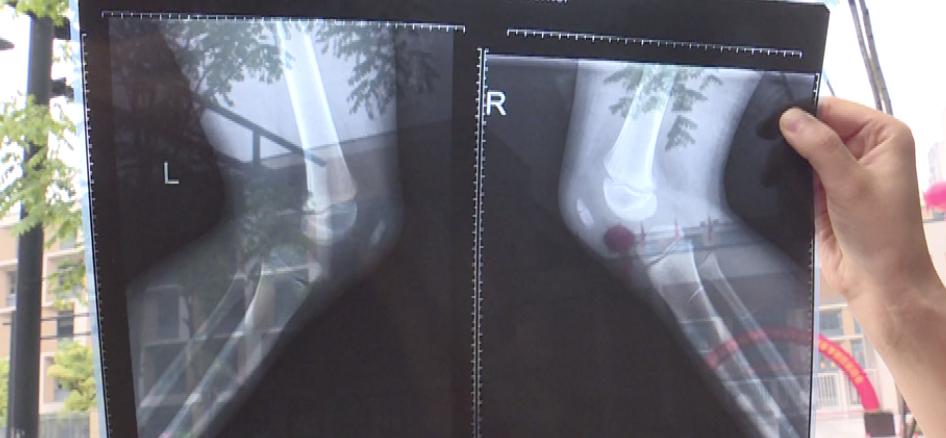

隨后,楊女士帶孩子去了醫(yī)院,被診斷為左側(cè)髕骨骨折。楊女士認(rèn)為,學(xué)校當(dāng)時(shí)沒有及時(shí)處理孩子的傷勢。